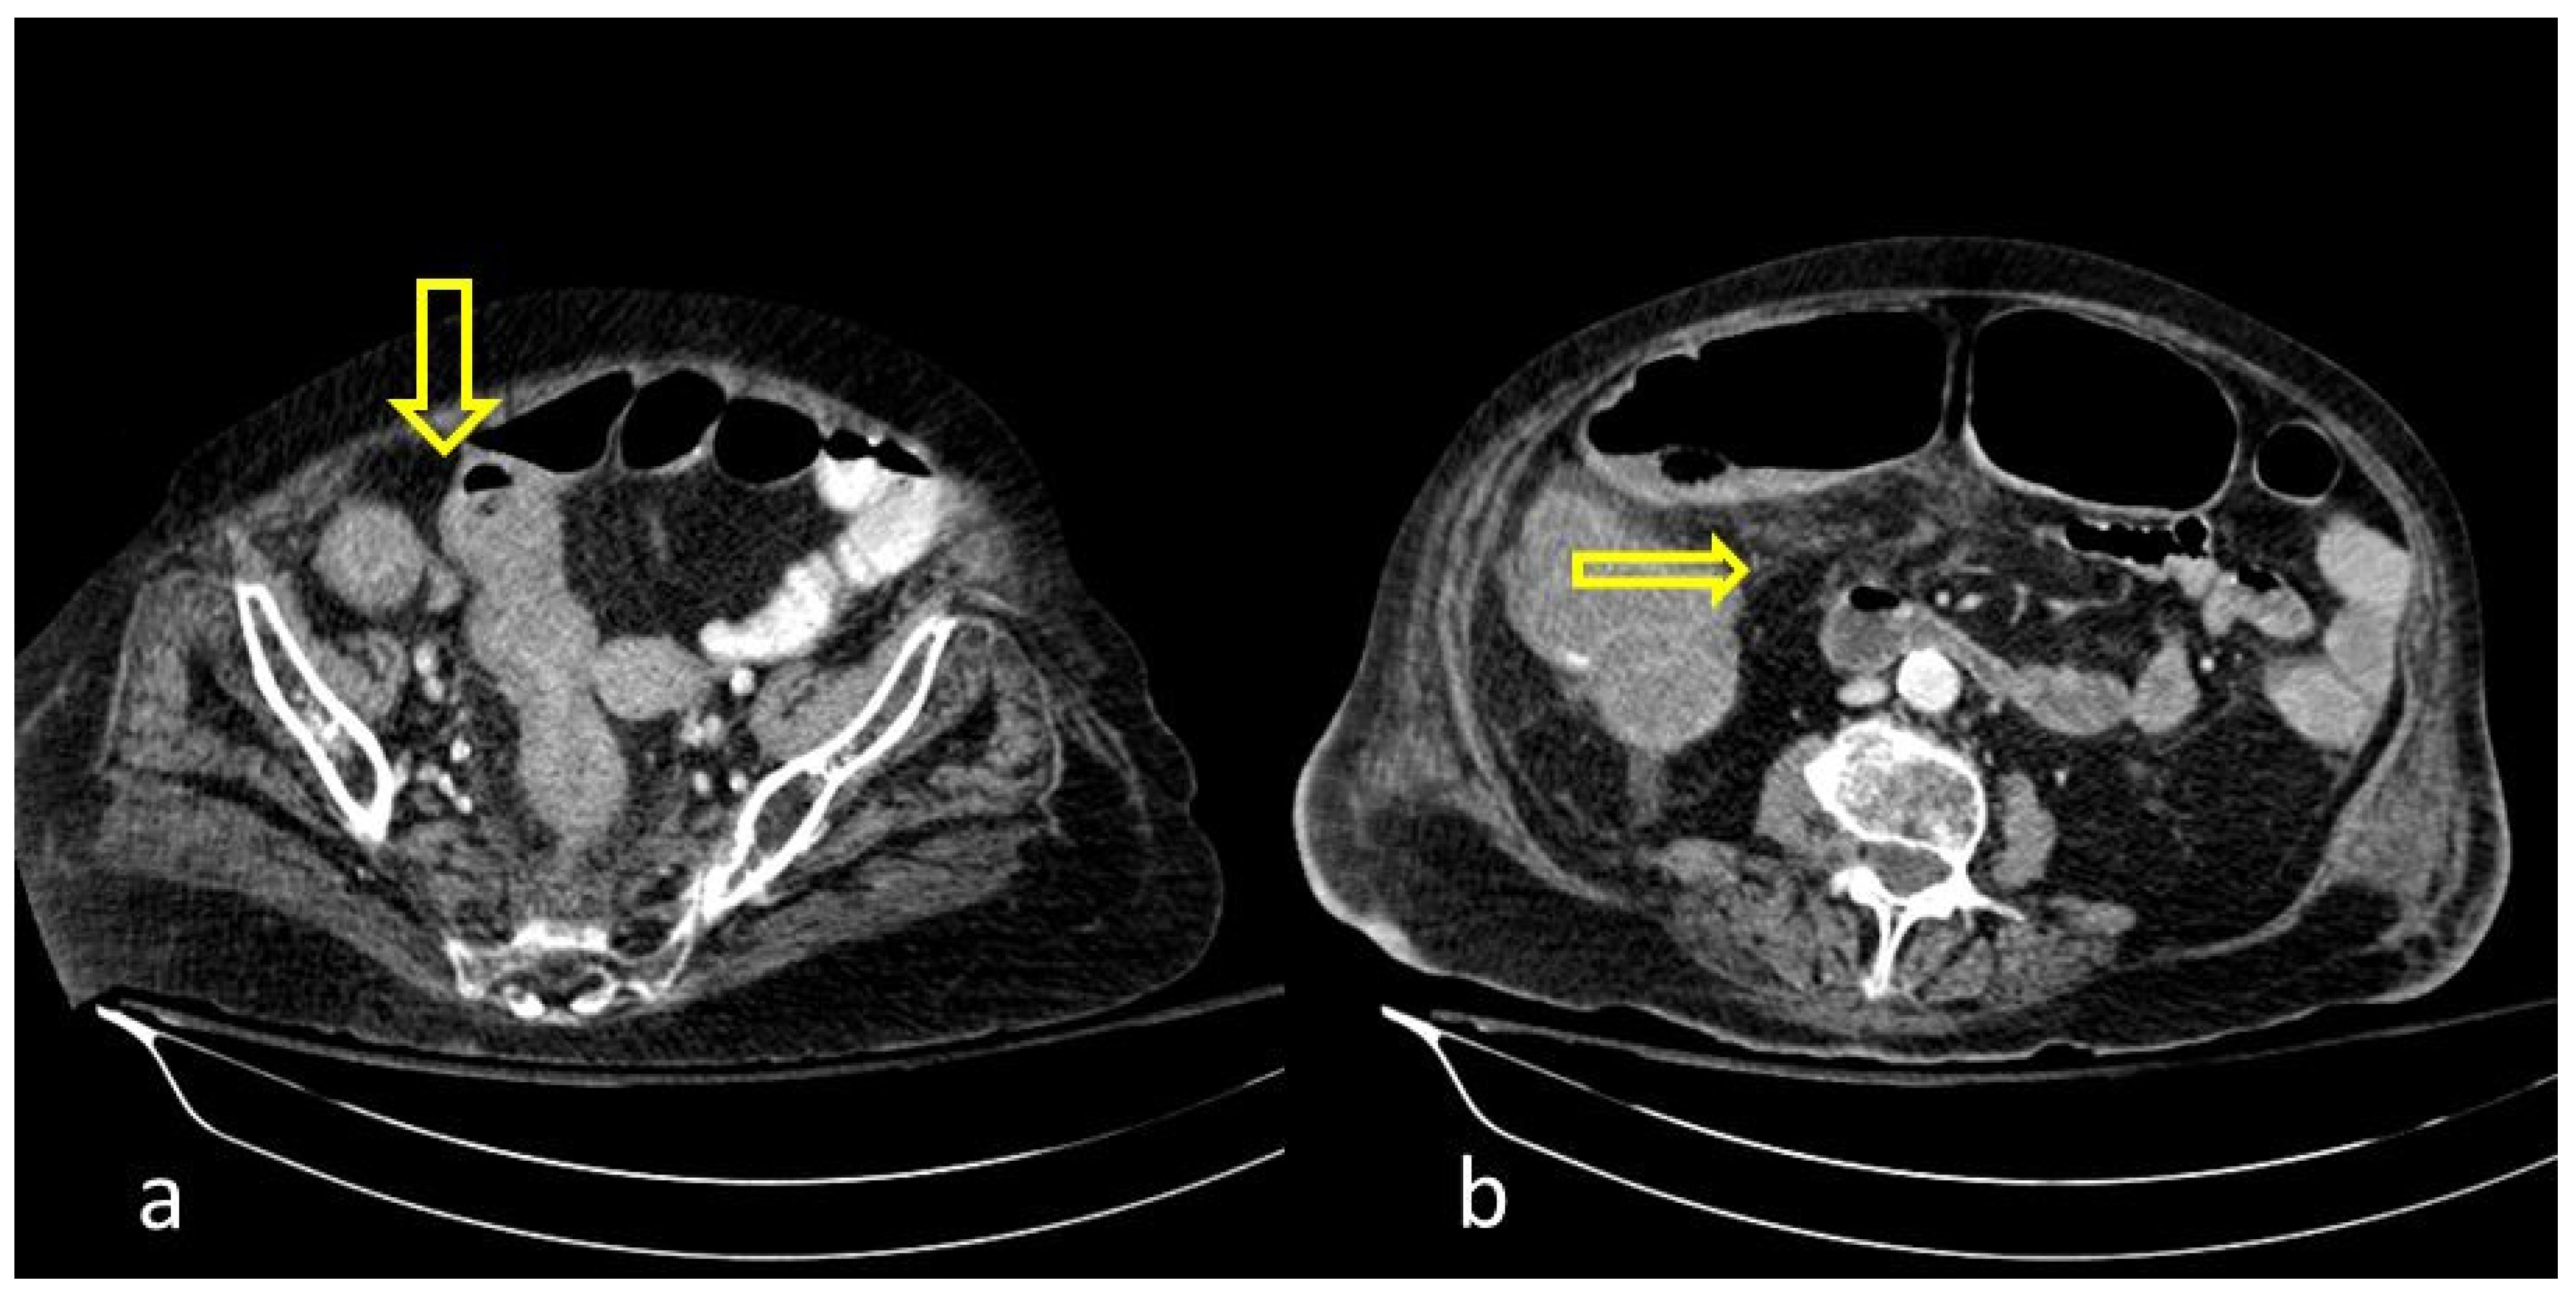

Figure 4. A 48-year-old female patient with COVID-19 pneumonia and no other comorbidities. CT scan depicted a thickened cecum with proximal fat stranding (yellow arrow).

A large bowel infection usually appears with diffuse circumferential and enhancing wall thickening (hyperenhancement) that can involve one or more segments of the colon (Figure 1 and Figure 2). Pericolic fluid or perintestinal fat stranding is common while pericolic lymphadenopathy is not (Figure 3 and Figure 4). If we suspect COVID-19-related colitis, clinical correlation is needed, and the detection of the virus in stools can establish the diagnosis.